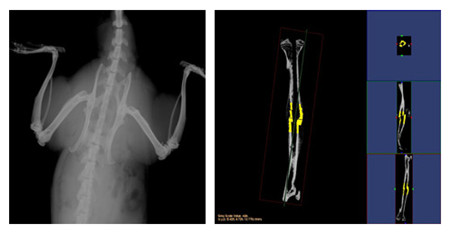

微量X光

X-Ray 即 X射线 。X射线是波长介于紫外线和γ射线 间的电磁辐射。X射线的特征是波长非常短,频率很高。因此X射线必定

是由于原子在能量相差悬殊的两个能级之间的跃迁而产生的。最初用于医学成像诊断和 X射线结晶学。利用美国Faxitron公司

MX-20,可检测骨组织标本及活体动物提供放大1-5倍图像,观察结构变化

1. 放大1-5倍图像

2. 完整的实验报告一份

结果示意图: